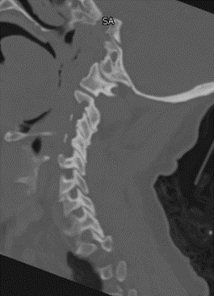

Things to Assess on Sagittal

Each of these should get its own, dedicated scroll through the entire sagittal CT scan

1) Atlanto-Occiptial Joint

Multiple measurements can be made, but on initial assessment, OK to assess 30000 ft view

Joint Congruence

Fracture of the Occipital Condyle

Anterior Soft tissue swelling - to assess hypothetical scenario of Atlanto-Occipital dislocation without fracture than has subsequently perfectly concentrically reduced

2) Dens

Assess for Fracture

Assess Atlanto-Dens Interval (ADI): <3mm: Nml; 3-5mm: Transverse Ligament Injury; >5mm: Complete Ligament Disruption

Posterior Atlanto-Dens Interval (PADI or “Space Available for the Cord” (SAC)): >13mm: nml

Note that there can be congenital narrowing that does not reflect a post-traumatic finding

3) Mid Sagittal Alignment

Each should get its own dedicated run through the CT Scan

Evaluate Anterior / Posterior Vertebral Lines, Spinolaminar Line, and Interspinous Line

Barring some allowance for degenerative change in the elderly, the lines should all be smooth, gentle transitions

4) Facets

Both Left and Right facets should get a dedicated run through the CT scan

Facets should “shingle” smoothly

Look for asymmetric widening between facets

5) Vertebral Bodies

Assess for vertebral body irregularities to suggest fracture

Assess spacing between vertebral bodies

Disc spaces should be symmetric

6) Spinous Processes Assess Spinous Processes for fracture